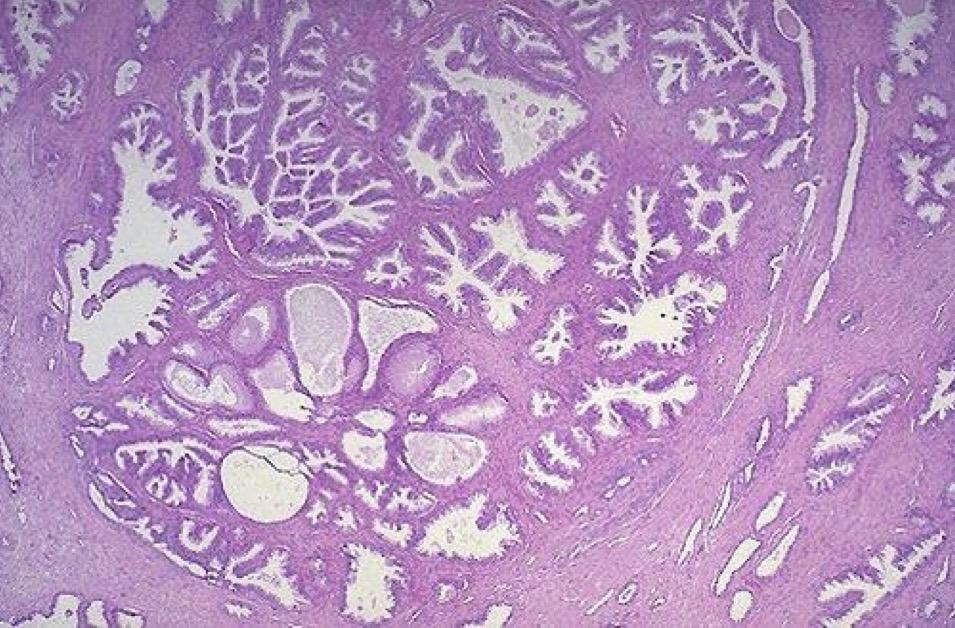

A- Urothelial papilloma

B- Papillary fronds with fibrovascular cores are lined by normal appearing urothelium

C- from benign epithelial tissue

A- identify

B- describe

C- originate from ?